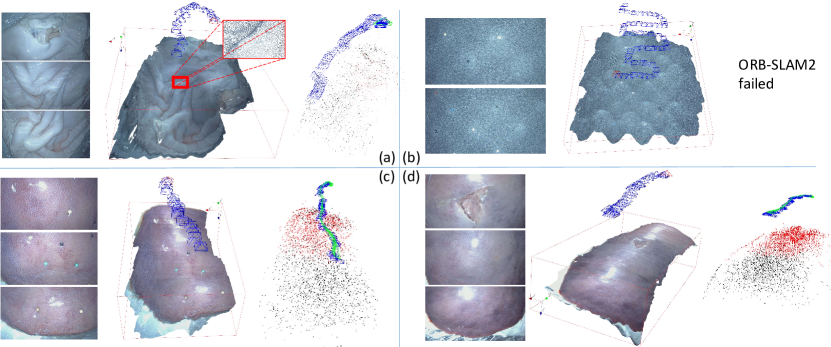

We first qualitatively tested our 3D reconstruction method on phantoms and ex vivo tissues, including porcine stomachs and livers. We used a KARL-STORZ stereo laparoscope (model number TipCam 26605AA) with a resolution of to capture stereo videos and performed the proposed 3D reconstruction method on the videos. The candidate disparity values for performing ZNCC matching are between and pixels. Details of the videos are provided in Tab. I. The results of our ex vivo qualitative experiments are shown in Fig. 8. Since down-sampling is not included in the reconstruction process, the obtained 3D models have the same resolution as the input image, which usually include millions of points and are able to provide rich details of the surface texture. Our results qualitatively look promising and accurate. We also employed ORB-SLAM2 [6] for comparison, which is one of the most famous open-source SLAM methods. In order to handle low texture, the key parameters of ORB-SLAM2 were set as follows: the number of feature points is 3000 per image, and the threshold for detecting FAST corner is 1. As shown in Fig. 8(a) and (c), ORB-SLAM2 succeeded in reconstructing the sparse environment and tracking the camera motion. However ORB-SLAM2 tracking lost in cases shown in Fig. 8(b) and (d) due to the low texture.

We also tested ORB-SLAM2 on the collected in vivo data, which performed well on most cases because the texture is generally richer than our ex vivo data. However, in the spine experiment we observed that ORB-SLAM2 failed to track the camera motion during the scan (see Fig. 13).